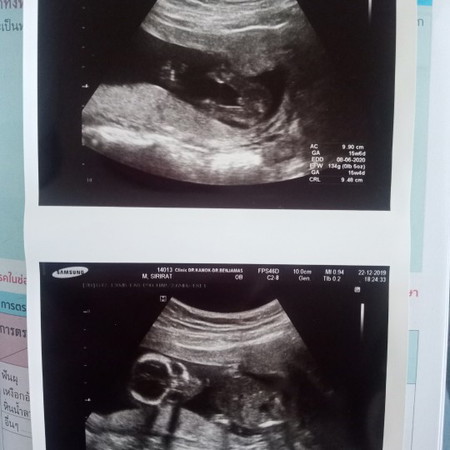

แบบนี้จะชายหรือหญิงนะ

คุณหมอบอกชาย 80% มีแหลมๆออกมา แม่ๆที่ซาวน์แล้วเห็นประมาณนี้ได้ชายหรือหญิงคะ? ?

ชายค่ะ